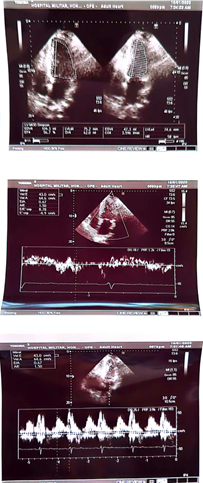

7 patients (5 male and 2 females with ages between 60, 65, 68, 60, 18, 22 and 95 years) were studied. Clinical criteria were used to determine the functional class according to the NYHA classification. . Laboratory analysis such as complete hematology with erythrocyte sedimentation rate (VES), C-reactive protein (CRP), D-dimer, Ferritin levels, NTproBNP, troponin I. Serum creatine, urea nitrogen, basal glycemia, Total cholesterol, HDL, LDL, Triglycerides, TGO, TGP, sodium, potassium, magnesium, T3, T4, TSH. Endothelial test through high resolution ultrasound with a 12 MHz transducer for reactive hyperemia through the radial artery: Baseline, post administration of sublingual nitroglycerin. Conventional echocardiogram, M-mode, Bidimensional, tissue Doppler. 12-lead electrocardiogram and AP and Lateral Chest Rx.

Case number 1: This is a 60-year-old male patient with a history of known hypertension for 10 years controlled with Candesartan plus hydrochlorothiazide 32/25 mg daily. Mixed dyslipidemia controlled with statin type atorvastatin 40 mg daily. Significant central obesity BMI of 35. Also, sedentary life. History of 4 inoculations with the Pfizer vaccine, he began to present with acute respiratory distress, palpitations, paroxysmal nocturnal dyspnea, orthopnea, saturation of 85% by oximetry. On physical examination: marked arterial hypotension 80/60 FC: 135 beats per minute Respiratory rate of 28 per minute acrocyanosis and on cardiac auscultation: rhythm Irregularly irregular with a more audible mitral regurgitation murmur at the apex of the heart radiating to the axilla. Lung auscultation: crackles from the middle third to the base of both lung fields. The electrocardiogram shows rapid atrial fibrillation rhythm at 135 beats per minute. Chest X-ray: Grade III-IV cardiomegaly with acute pulmonary edema. An echocardiogram was performed, showing findings compatible with dilated cardiomyopathy with left ventricular ejection fraction of 10%. Global hypokinesia, in doppler moderate-severe mitral regurgitation. Moderate-severe tricuspid regurgitation with pulmonary systolic pressure of 90 mmHg. Tissue Dopplar significant increase in left intraatrial pressure 25. In addition, the following laboratory analyzes were performed: Complete blood count: leukopenia: 2,000 leucocytes. Hb: 12.5 g/dl. Thrombocytopenia: 107,000 platelets, severe eosinopenia and lymphopenia. Elevated D-dimer 2.0 (normal value up to 0.50) Elevated NtproBNP 3,500 (normal up to 300). C-reactive protein of 32 Normal up to 10. Ferritin of 750 (normal up to 250). Creatinine: 3.2 mg/dl Urea: 70, TGO: 110, TGP:115.

Control echocardiogram is performed

We can appreciate the amazing size left ventricle and normal global and segmental contractility with normal left ventricular ejection fraction (75%). Previous 10%. In addition, the patient was asymptomatic from the cardiological point of view. In such a way that all the medication that was started for the treatment of dilated cardiomyopathy was suspended, such as: Sacubitril/valsartan, furosemide, aldactone, ivrabadine, metoprolol, oral anticoagulants. The only treatment for her arterial hypertension was left with candesartan 16 mg per day and rosuvastatin 40 mg at night for mixed dyslipidemia. The following 6 patients 5 are male with ages: 28, 33, 35, 85 and one female: 95 years of age whose ejection fractions were similar 18, 17, 16 and 15% respectively and their evolution is similar to that of First case with an echocardiographic and clinical evolution to total normality. All patients currently lead a completely normal life.1-3